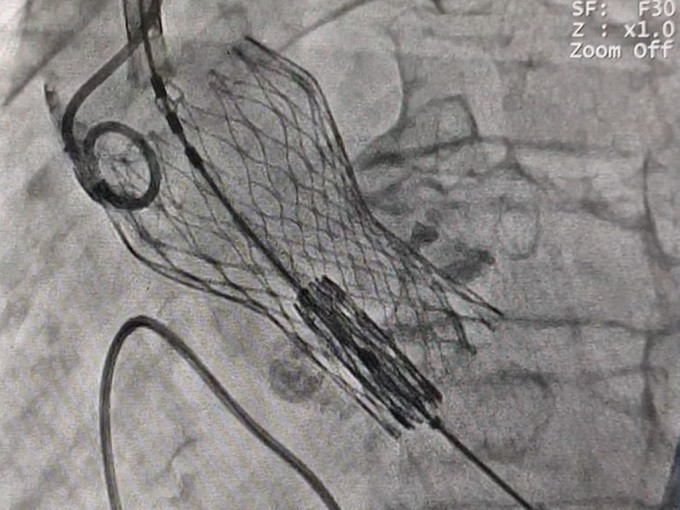

Sáng 18/10, bệnh nhân được can thiệp thay van trong van qua đường ống thông và sử dụng loại van nở trên bóng đặt trong van tự nở lần trước (đây là 2 loại van cơ chế khác nhau trong TAVI). Ông T. trở thành ca TAVI-in-TAVI lần đầu tiên ở Việt Nam. Thủ thuật hoàn thành trong khoảng thời gian 30 phút tính từ lúc chọc mạch đùi. Bệnh nhân chỉ cần gây ngủ và tỉnh ngay sau thủ thuật.

PGS.TS Phạm Mạnh Hùng, Viện trưởng Viện Tim mạch Việt Nam, cho biết đây là trung tâm đầu tiên trên cả nước thực hiện một cách độc lập kỹ thuật TAVI với van trên bóng. Kỹ thuật thành công mở nhiều cơ hội cho bệnh nhân Việt Nam. Đáng nói, cách đây vài năm, bác sĩ tim mạch can thiệp không bao giờ ngờ tới có thể thực hiện được kỹ thuật này.